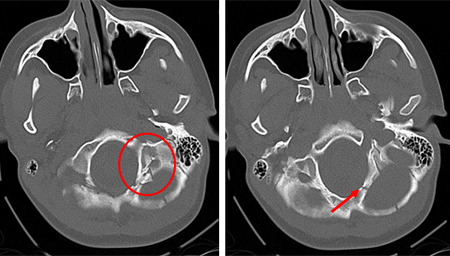

Skull fractures

Fracture of temporal bone

Fracture of temporal bone extending into foramen ovale